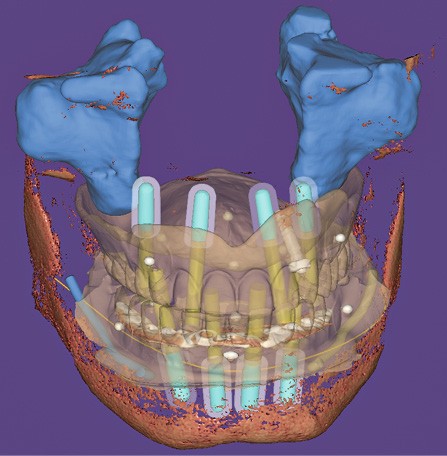

Les guides à étages sont des guides chirurgicaux statiques où chaque élément remplit un rôle lors de la pose des implants, déterminé lors de la phase de planification implantaire et de la conception de ces pièces. Une majorité de logiciels de conception par ordinateur rend aujourd’hui possible leur création, mais nécessite toutefois une expérience informatique avancée souvent réservée aux laboratoires de prothèse (fig. 1).

Un premier étage, appelé guide base, est fixé sur le maxillaire à implanter et servira de socle pour les étages supérieurs à empiler (fig. 2). Il doit être aussi rigide que stable pour supporter les contraintes pendant toute la durée de l’intervention : celles du forage implantaire comme celles des poses et déposes des étages supérieurs. Son bon positionnement est donc crucial car il déterminera celui des autres étages. Il peut également servir de repère en fin de procédure, tel un guide de scannage, pour réaliser une empreinte optique (fig. 3). Les appuis sont aussi divers qu’avec un guide statique conventionnel :

- appui dentaire : il est le plus fiable car son positionnement est permis grâce à des points fixes (fig. 4). Il reste bien sûr dépendant de la précision de l’alignement entre le STL de l’empreinte optique et le DICOM de l’examen CBCT ;